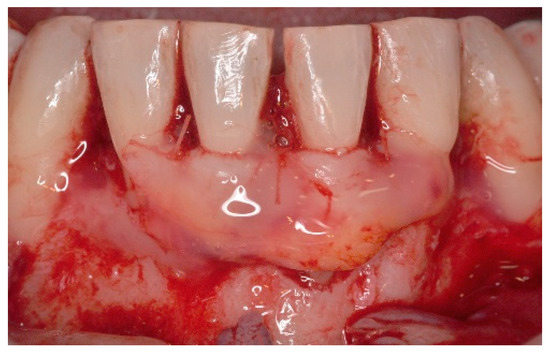

5. Materials and Methods